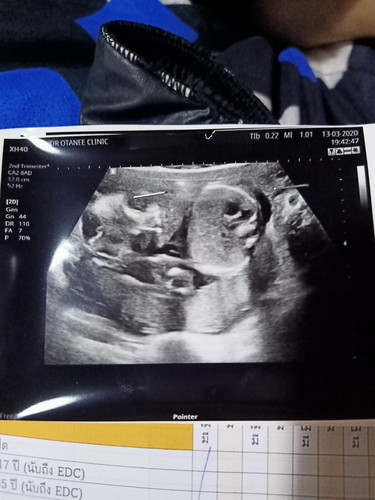

ดูเพศให้หน่อยค่ะดูไม่ออก ค่ะ หญิง หรือ ชาย

น่าจะผู้ชายนะค้ะ😊😊

ช